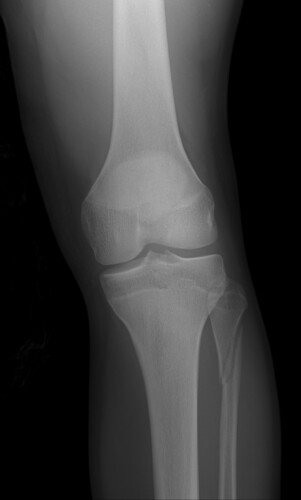

Eu sou o Luan de Couet Marafon, zagueiro do Caxias Sub 17 e sofri uma fratura grave no tornozelo esquerdo durante um jogo e preciso fazer uma cirurgia. Estou fazendo essa vaquinha para ajudar a cobrir o valor do procedimento cirúrgico, exames, fisioterapia e demais despesas. Quem puder ajudar com qualquer valor ou compartilhar, ficarei grato!